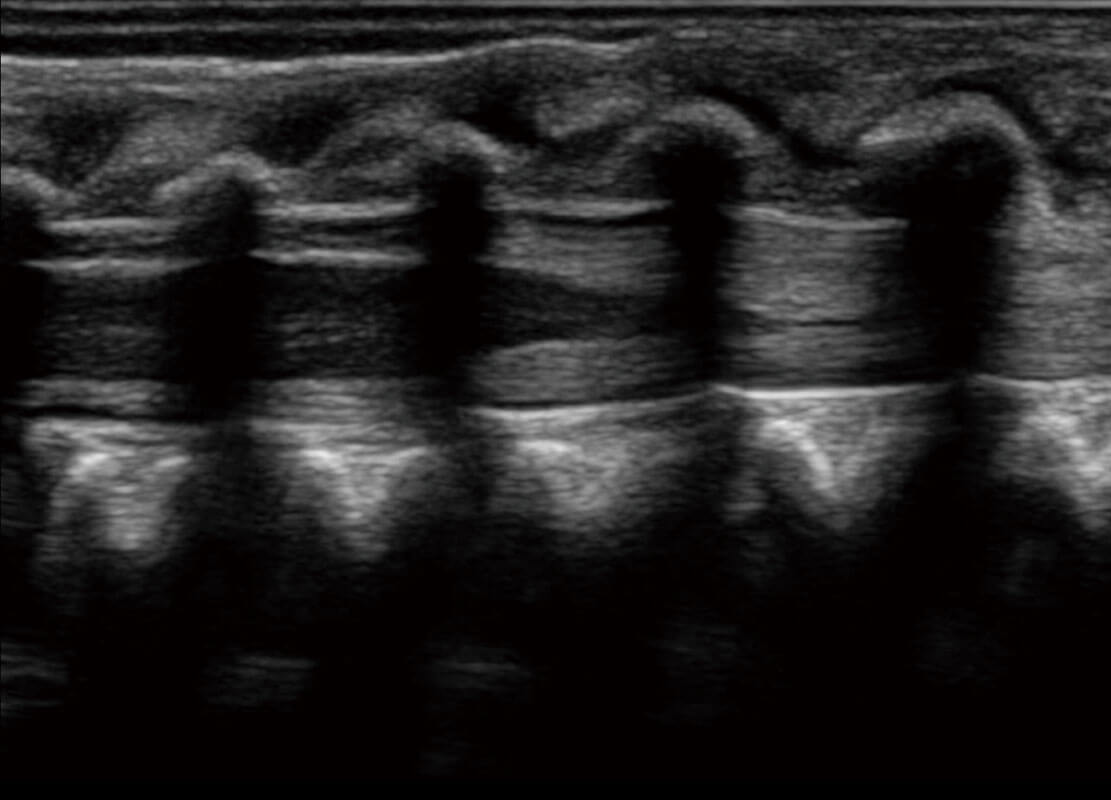

• 新生儿脊髓圆锥